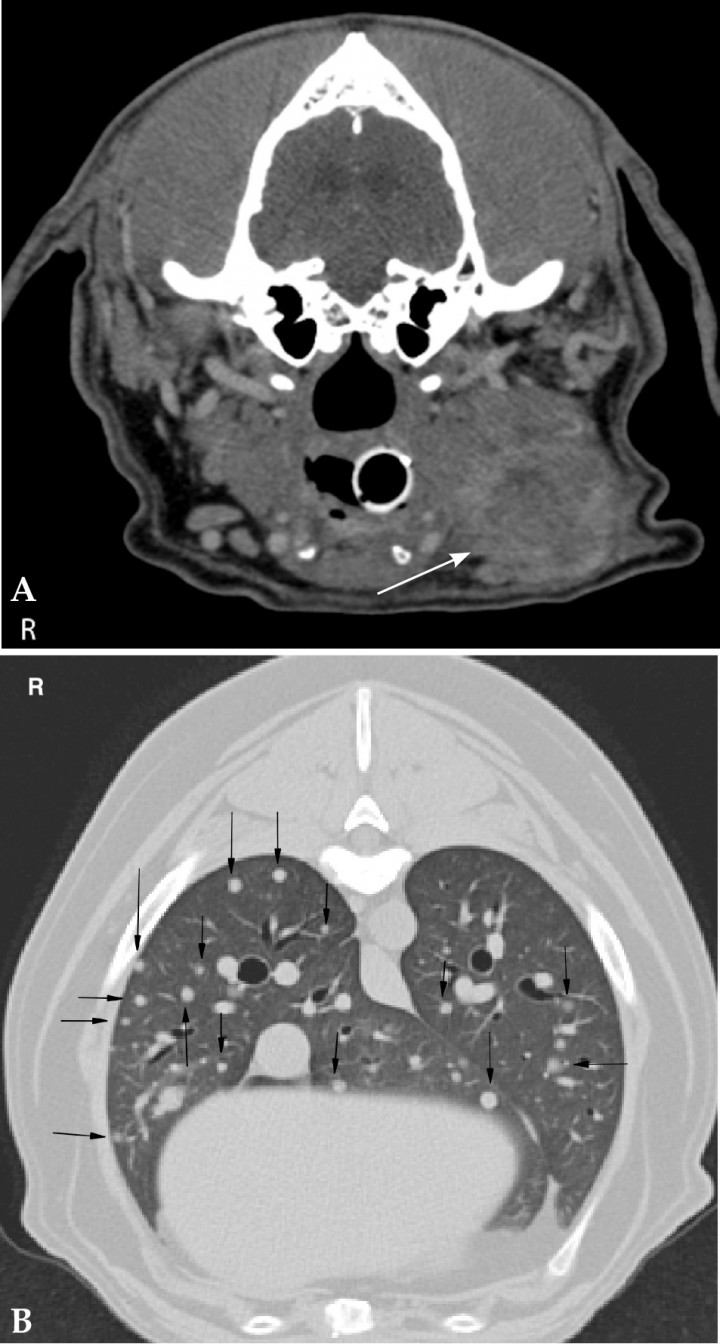

Due to the close relationship of anatomical structures of the neck, cross sectional imaging provides important information of origin and extension of neoplasia in this region. Thyroid gland tumour is the most common neoplasia in the neck and can occur from the base of the tongue to the base of the heart. Although ultrasound is a good screening tool, CT or MRI are indicated if surgical resection is considered. The masses are usually highly vascularized, heterogeneous and can contain regions of dystrophic mineralization. CT findings of carotid body and thyroid tumours are different based on anatomical location. Carotid body tumours have a dorsolateral location to the larynx at the level of the bifurcation of the common carotid artery (Fig. 3A). Thyroid masses are located more caudally (Fig. 3B).[ Mai W, Seiler GS, Lindl-Bylicki BJ et al.: CT and MRI features of carotid body paragangliomas in 16 dogs. Vet Radiol Ultrasound 2015; 56:374-383. [PubMed] , Taeymans O, Penninck DG, Peters RM: Comparison between clinical, ultrasound, CT, MRI, and pathology findings in dogs presented for suspected thyroid carcinoma. Vet Radiol Ultrasound 2013; 54:61-70. [PubMed] ]

<p>(A) 8 year-old Golden Retriever with a carotid body tumour on the right side. Transverse CT soft tissue window post contrast image of the neck at the level of the carotid bifurcation (white arrows) and mandibular salivary glands (black asterisks). There is a poorly demarcated mass (white asterisk) with mild heterogeneous contrast enhancement on the right dorsolateral aspect of the larynx causing lateral displacement of the right carotid arteries. (B) Transverse soft tissue window post contrast image of the neck of a 13 year-old mixed breed dog with a mass at the level of the right thyroid gland (white arrow). The mass shows marked heterogeneous contrast enhancement and a central pinpoint mineralization. The left thyroid gland is unremarkable (black asterisk). R: right.</p>

Figura 3

(A) 8 year-old Golden Retriever with a carotid body tumour on the right side. Transverse CT soft tissue window post contrast image of the neck at the level of the carotid bifurcation (white arrows) and mandibular salivary glands (black asterisks). There is a poorly demarcated mass (white asterisk) with mild heterogeneous contrast enhancement on the right dorsolateral aspect of the larynx causing lateral displacement of the right carotid arteries. (B) Transverse soft tissue window post contrast image of the neck of a 13 year-old mixed breed dog with a mass at the level of the right thyroid gland (white arrow). The mass shows marked heterogeneous contrast enhancement and a central pinpoint mineralization. The left thyroid gland is unremarkable (black asterisk). R: right.